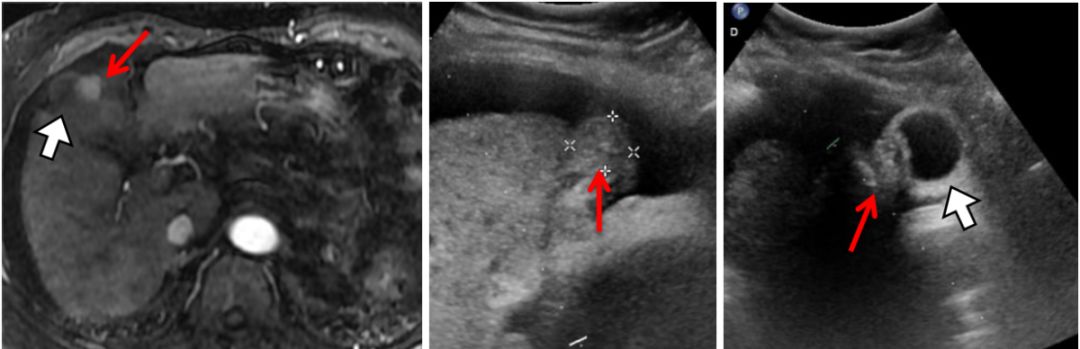

由于肝脏特殊的生理解剖,临近危险器官的特殊部位以及影像显示不清的肝肿瘤,一直是影像引导下经皮消融治疗的难点或“禁区”。 近日,我院放射科介入病房邵海波教授、田玉龙主治医等在麻醉科的大力配合下,为一名复杂的肝癌患者进行了影像引导下的经皮微波消融治疗。手术仅历时1.5小时,术后3天患者即顺利出院。 患者为62岁女性,半年前诊断为原发性肝癌,为肝左叶单发病灶,曾行经导管肝动脉化疗栓塞和微波消融治疗,术后病灶完全灭活。本次入院MRI检查发现新发肿瘤,肝内共有4个活性病灶,分别位于心缘旁、膈顶、胆囊旁等“危险部位”,血供较差,TACE治疗控制不佳,经详细讨论,决定采用经皮微波消融治疗。由于病变位置特殊,加之平扫CT或超声均不能清晰的显示全部病灶,大大增加了消融治疗的难度和风险。术中,治疗团队采用腹水隔离、CT/超声双引导进针监测、解剖标记定位、低功率间断消融等多种辅助手段相结合,对全部4处病灶进行了安全、精准的微波消融治疗,手术历时1.5小时,术后3天患者顺利出院。 图1. 临近心脏的膈顶部病灶,水隔离保护下消融 图2. 临近包膜的膈顶部病灶,水隔离保护消融 图3. 紧邻胆囊病灶,超声引导和监测下低功率间断消融 图4. CT和超声均显示不清的病灶,采用CT引导解剖标记定位消融 图5.肿瘤消融治疗是指利用消融治疗针穿刺肝肿瘤,针尖能够产生电磁波而使周围组织升温至80度以上的高温,从而杀灭肿瘤。 图6.危险部位肿瘤是指当肿瘤靠近膈顶、心脏、胃、肠管、胆囊、以及肝门部等部位时,对肿瘤进行消融就容易损伤相应的器官,引起并发症。因此这些部位的肿瘤称为危险部位肿瘤。 此病例癌症病灶位于膈顶部、心脏旁、胆囊旁、肝门部、大血管附近,肝边缘近胃肠道、外凸近腹壁,治疗难度大,技术复杂、成功率低、风险高。介入病房开展水隔离技术、胆管冷却技术、术中引流技术、造影增强定位技术、解剖标记定位技术、复合影像导航穿刺和监视技术等新技术对危险部位和复杂病灶进行成功的经皮消融治疗,几乎做到肝脏肿瘤消融无禁区、无死角。 近年来,影像引导下经皮微波消融治疗已成为肝癌/肝转移癌、肺癌、肾癌等实体肿瘤最为有效的微创治疗手段之一,具有创伤小、恢复快、疗效确切、可重复治疗等优点。据统计,2018年,放射科介入病房利用各种辅助技术处理复杂或高危部位肿瘤41例,疗效显著且无并发症发生,与前期未应用辅助技术的病例相比,完全消融的比率显著提高(93.5% vs.78.5%),不良反应发生率显著降低。 我院放射科介入病房自2004年开始开展影像引导下肝癌的射频/微波消融治疗,在放射科副主任苏洪英教授的领导下,不断突破技术难点,治疗水平逐年提高。科室选派技术骨干到国外学习先进技术,其中本例手术的术者邵海波教授就是在我院中青年骨干培训计划的支持下,在哈佛医学院/麻省总医院进行了为期近2年的消融治疗培训和研究后,回国将所学更好地应用于临床。目前,科室在影像引导下经皮肝肿瘤微波消融领域处于国内领先水平。